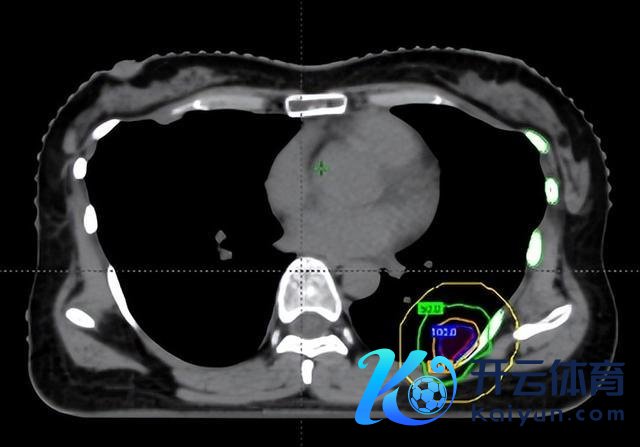

在调停前,团队通过四维CT对三个病灶进行精确定位,尤其是紧贴肋骨的阿谁病灶,连与肋骨之间极其微小的裂缝齐被明晰标注出来。

随后参加最中枢的剂量筹算步伐。胡英教训与李忠伟、雷大明物理师反复推演射澄莹径和强度溜达,把高剂量区域严格法例在肿瘤规模内,同期让剂量在极短距离内速即着落。不错解析为,在体内完成了一次“毫米级雕琢”:肿瘤被精确障翳,而近在目前的肋骨却被保护在安全规模内。